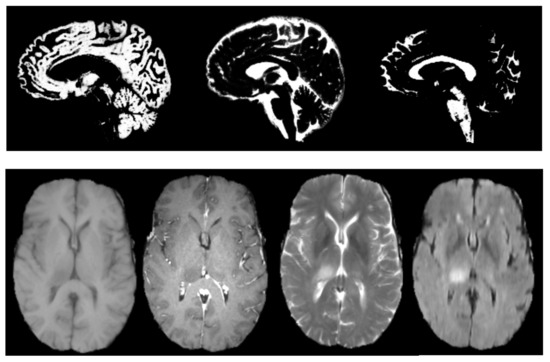

4.1. Attention Deficit Hyperactivity Disorder Diagnosis

4.2. The Brain Tumour Segmentation on BRATS 2017